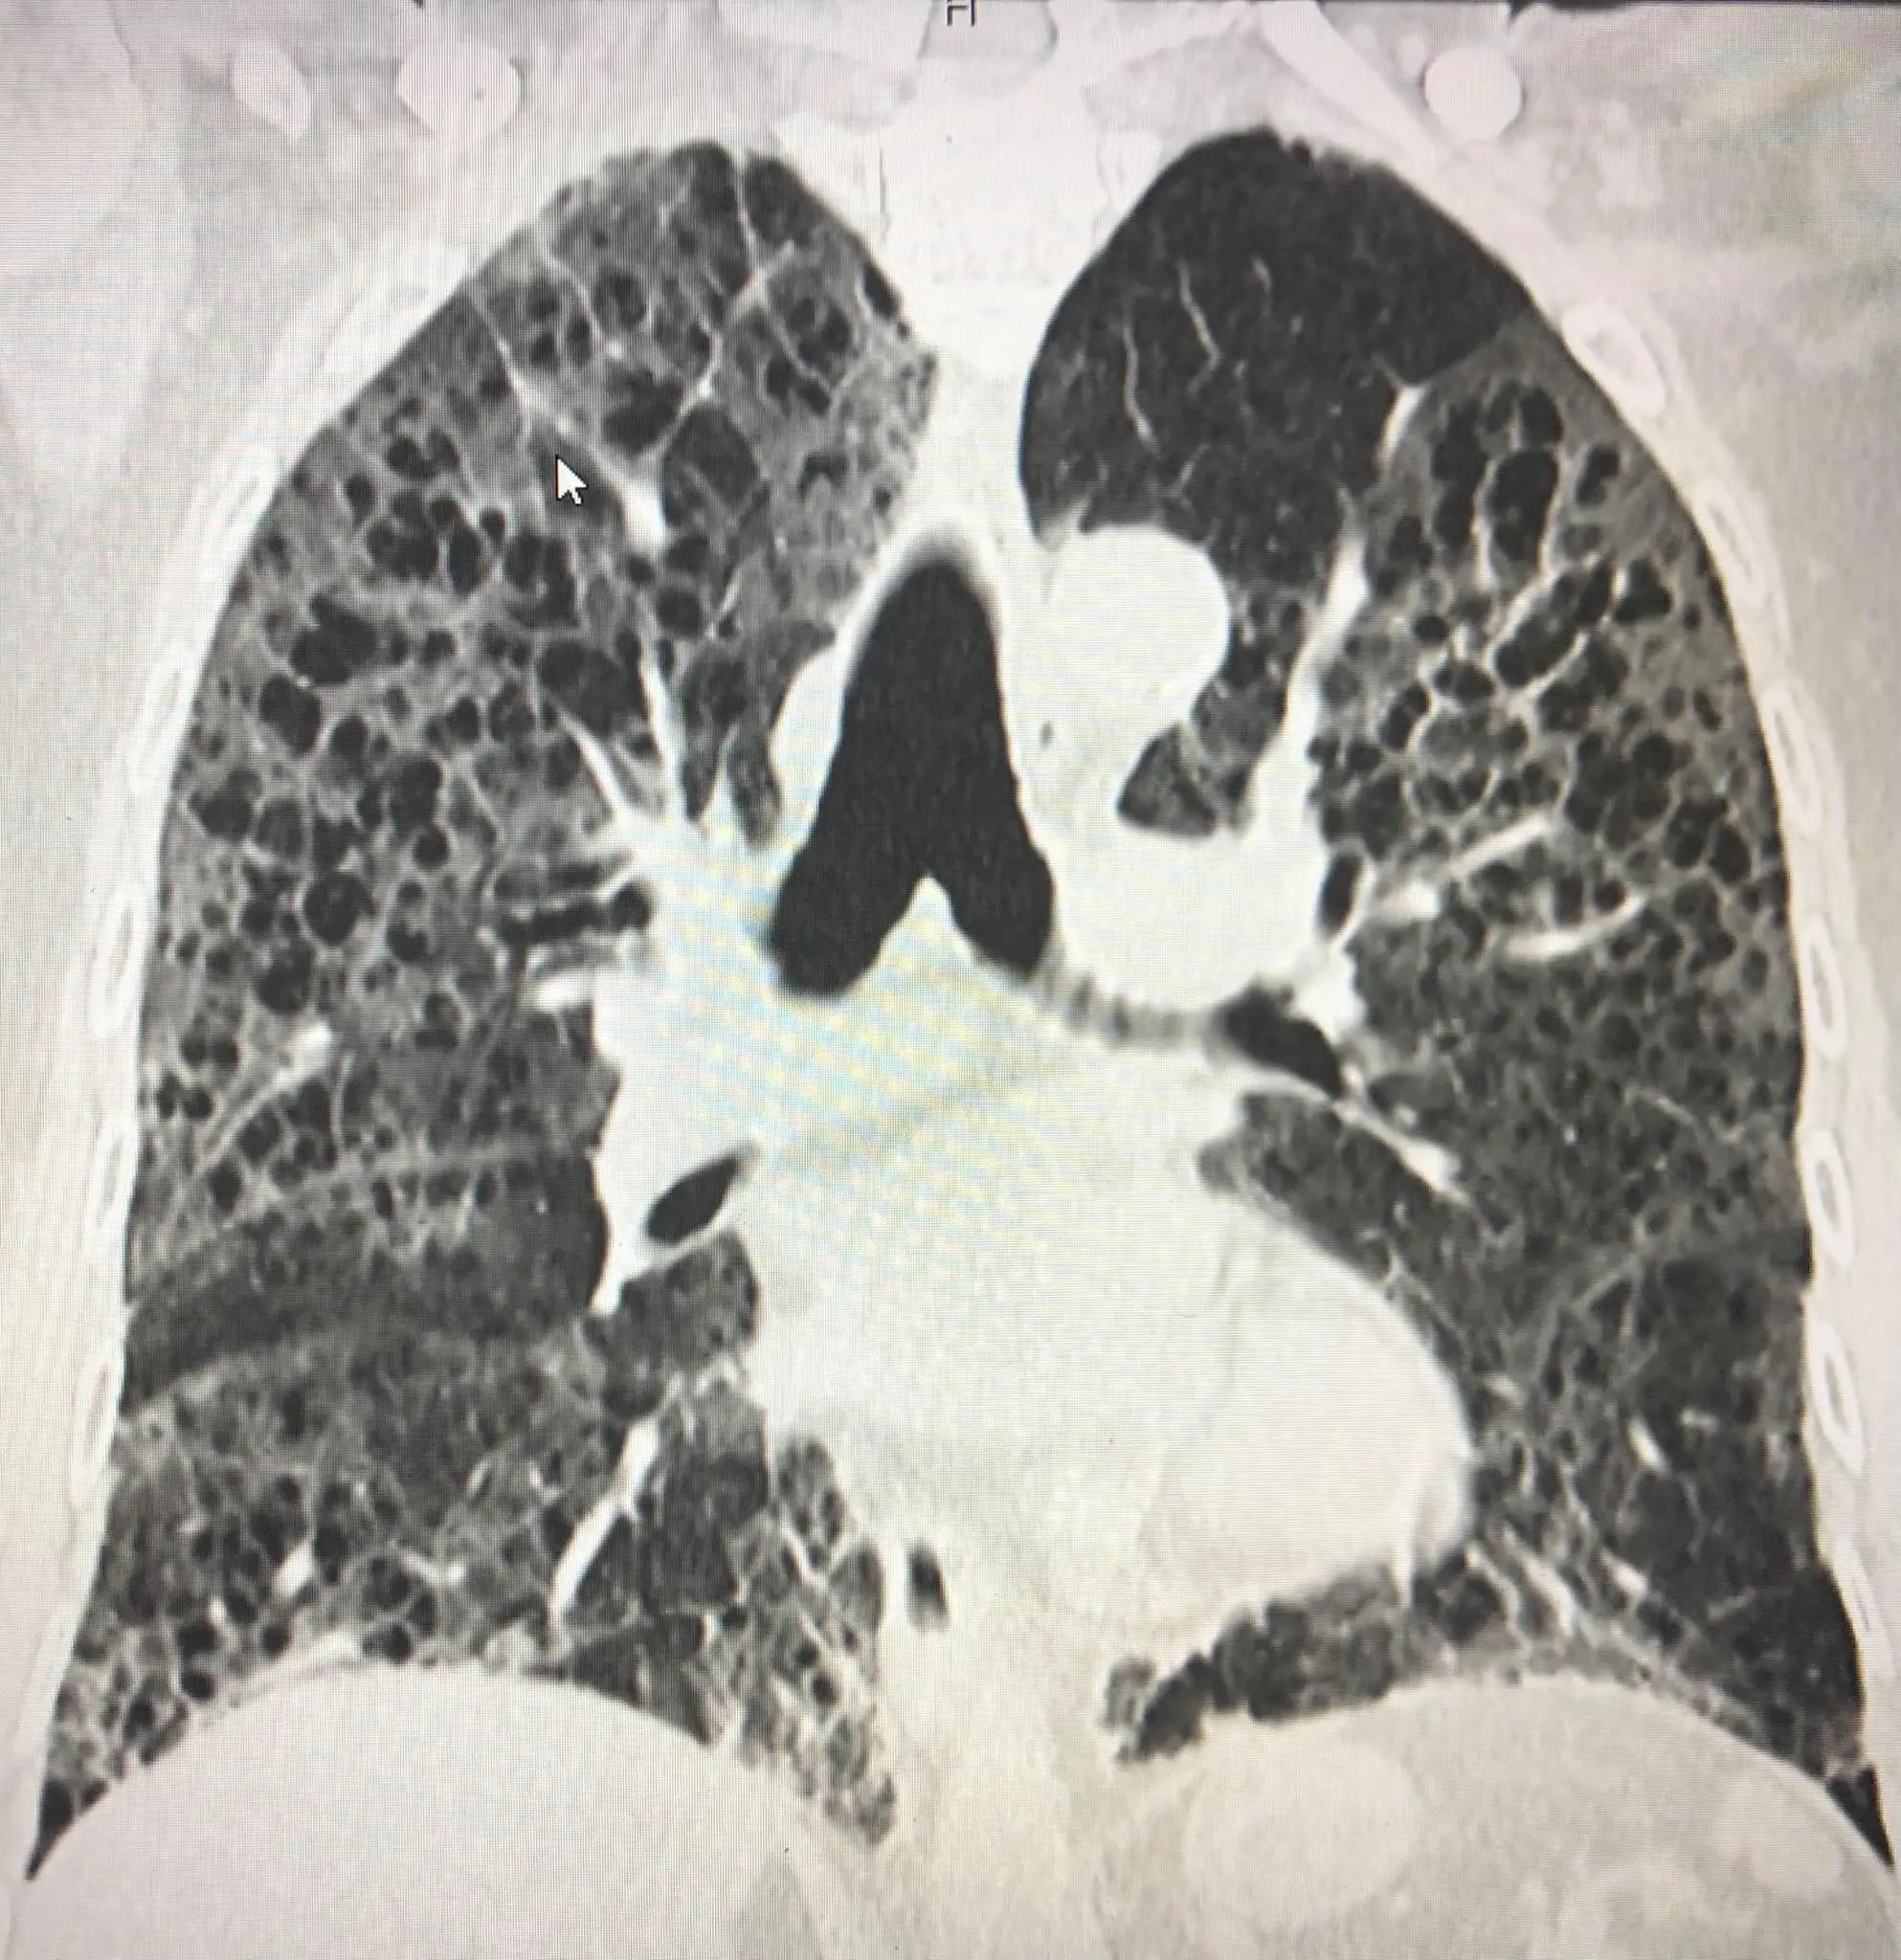

ผู้ป่วยชายไทยอายุ 80 ปี ปกติแข็งแรงดี ไม่มีประวัติป่วยเป็นโรคปอด ไม่สูบบุหรี่ เมื่อวันที่ 16 เมษายน 2564 ป่วยเป็นโรคโควิด-19 โดยลูกเป็นคนนำเชื้อมาให้ผู้ป่วยและคนในครอบครัวรวมทั้งหมด 7 คน เข้านอนรักษาในโรงพยาบาลด้วยปอดอักเสบรุนแรง เอกซเรย์ปอดมีฝ้าขาวทั้ง 2 ข้าง (ดูรูป) ทำคอมพิวเตอร์สแกนปอดพบเนื้อเยื่อปอดอักเสบรุนแรง มีทั้งฝ้าขาว รอยโรคเหมือนร่างแห และลักษณะผิดปกติคล้ายรังผึ้ง กระจายทั่วปอด (ดูรูป) ผู้ป่วยได้รับการรักษาเต็มที่ โชคดีที่ไม่ต้องใส่เครื่องช่วยหายใจ ต้องใช้ออกซิเจนมากถึง 10 ลิตร/นาทีตลอดเวลา นอนในรพ.ถึงวันที่ 22 พฤษภาคม 2564